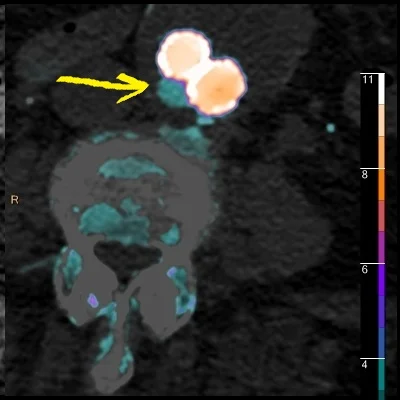

Fusion image nicely depicts the endoleak